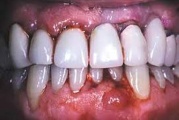

Parodontiit